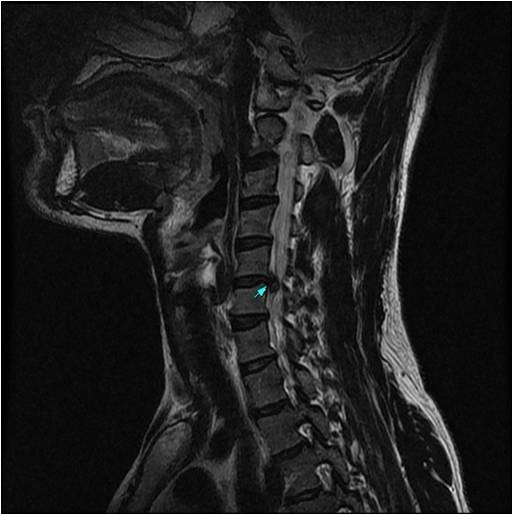

![]()

경추에 추간판 손상이 생기면 목이나 어깨 뒤쪽에 통증이 생기기도 하고, 한쪽 팔이 저리거나 얼얼한 느낌이 들거나 힘이 빠지는 느낌 등의 감각이상이 나타날 수도 있다.